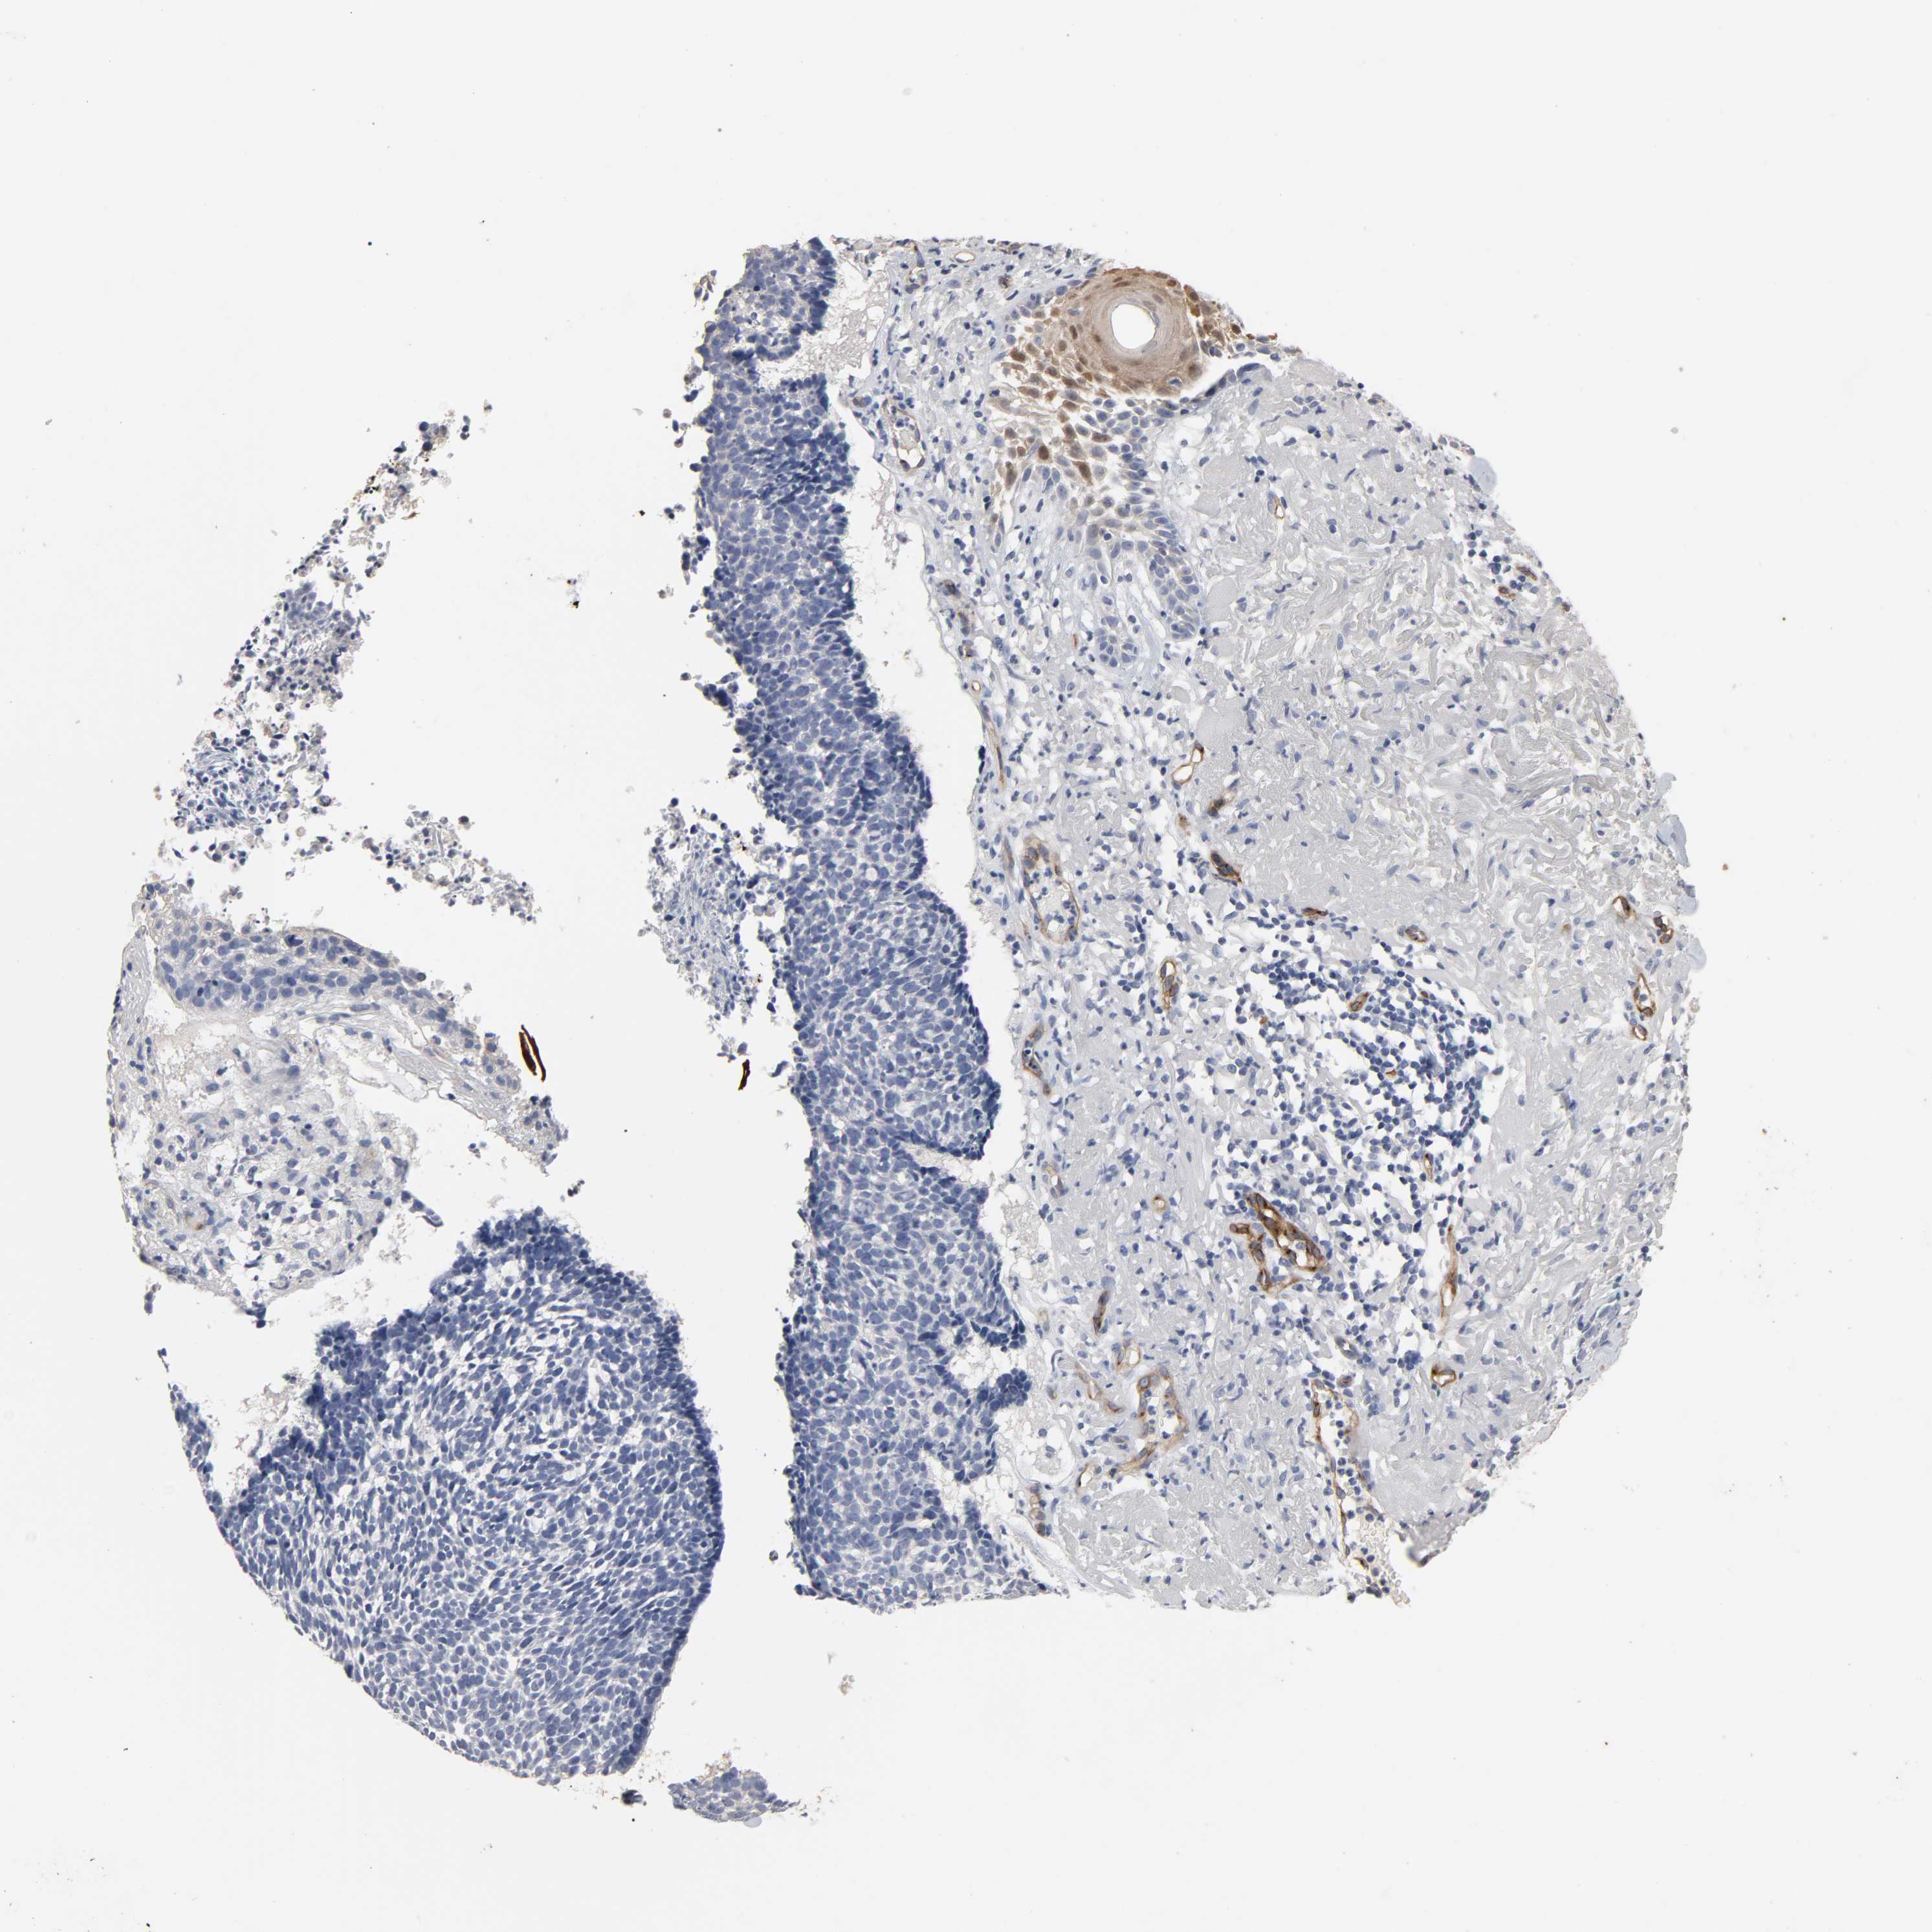

SKIN CANCER - Protein expressioni

A mouse-over function shows sample information and annotation data. Click on an image to view it in a full screen mode. Samples can be filtered based on level of antibody staining by selecting one or several of the following categories: high, medium, low and not detected. The assay and annotation is described here.

Antibody stainingi

Antibody staining in the annotated cell types in the current human tissue is reported as not detected, low, medium, or high, based on conventional immunohistochemistry profiling in selected tissues. This score is based on the combination of the staining intensity and fraction of stained cells.

Each image is clickable and will lead to virtual microscopy that enables deeper exploration of all samples and also displays staining intensity scores, fraction scores and subcellular localization as well as patient and tissue information for each sample.

Antibody CAB004028

Staining

High

Medium

Low

Not detected

Intensity

Strong

Moderate

Weak

Negative

Quantity

>75%

75%-25%

<25%

None

Location

Nuclear

Cytoplasmic/membranous

Cytoplasmic/membranous,nuclear

Squamous cell carcinoma, NOS

Basal cell carcinoma